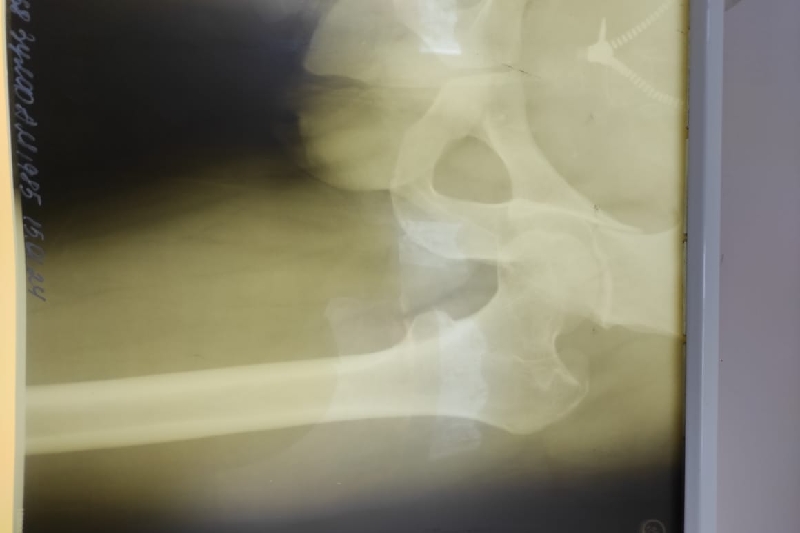

I am fundraising for my brother, who has gotten into a horrible car collision for work, hours away from his family. He is currently in the hospital and is expected to be there for 1 month, and will be bed-ridden for another 3 months after discharge.